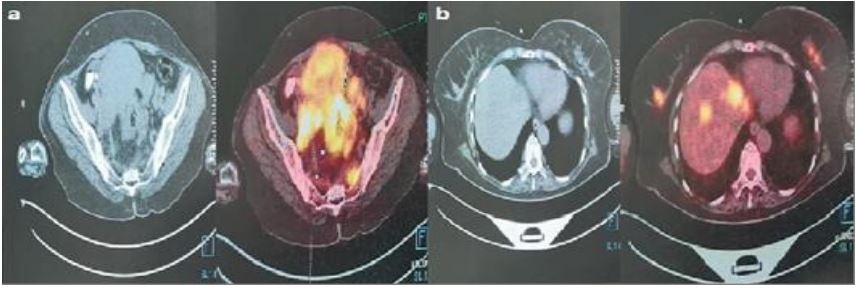

A married women patient aged 58 years applied to our hospital with a diagnosis of rectal cancer in an external health center. In the general examination of patient there were icterus an the Eastern Cooperative Oncology Group (ECOG) performance score of patient was three. The patient was hospitalized having carcinoembryonic antigen (CEA): 299 ng/ml (normal, 0-3 ng/ml), Carbohydrate Antigen (CA) 15-3: 18.1 U/ ml (normal, 0-31.3 U/mL), bilirubin: 2.44 mg/dL (normal 0.18-1.20 mg/dL) and International Normalized Ratio (INR): 2.9 (normal, 0.9-1.3) in her laboratory. The patient applied to another healthcare center with the complaints of diarrhea and weight loss that started about three months ago, and upon undergoing colonoscopy, it was reported that the patient had polypoid lesions in 6 cm of the rectum, mass lesion at 10-15 cm, and irregular mucosa at 20 cm. The patient’s three focal pathology reports were reported as moderate adenocarcinoma. In Positron Emission Tomography-Computer Tomography (PET-CT), besides a primary mass of 20 cm starting from the distal rectum-proximal anal canal to the distal of the sigmoid colon; there were inferior retropharyngeal Lymph Node (LN) metastasis, inferior jugular LN metastasis, pulmoner metastasis, widespread bone metastasis, liver metastases, intraabdominal metastases and mass lesions in both breast parenchyma (Figure 1). A tru cut biopsy was performed from both breasts in terms of synchronous mass or metastasis in the breast defined in PET-CT. Histopathologically atypical pleomorphic cells with hyperchromatic nucleus, some with distinct nucleolus, large cytoplasm in invasive stroma, partly solid islands and tumoral structures with gland-like structures partly were observed among sparse normal ductus structures in the samples taken from both breasts. The immunohistochemical study resulted in CDX2 diffuse nuclear positive, e-caderin positive, Estrogen Receptors (ER) and Progesterone Receptors (PR) negative, p63 negative, Cytokeratin (CK) 7 and CK20 negative, CerbB2 negative (score 0) in tumoral elements (Figures 2,3). The supportive treatment was provided to the patient as the ECOG performance score of the patient was 3, and the bilirubin and INR levels in the admission laboratory test were high. The patient whose performance worsened in the follow up died three months after the diagnosis.

Figure 1: In PET-CT screenings, a: Hypermetabolic primary mass areas were observed in the rectum. b: Metastatic masses with FDG uptake were observed in both breasts.